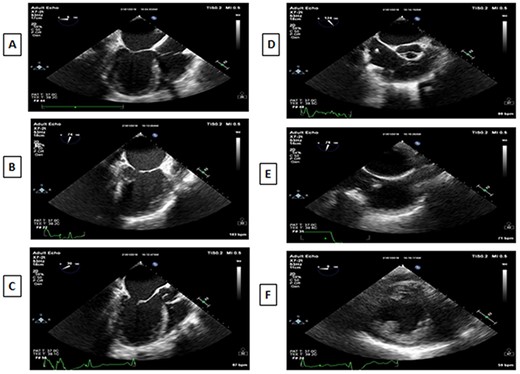

TEE views in a patient with dextrocardia with SI are different than the standard views. In the midesophageal four-chamber view at 0°, the right atrium and the right ventricle are on the right side of the display (Fig. 2A). The midesophageal two-chamber view, usually obtained at a multiplane angle of 90°, is identical to the view seen in a patient with situs solitus (Fig. 2B). The midesophageal aortic valve long-axis view (LAX) was obtained at a multiplane angle of 30–40° (Fig. 2C), while the midesophageal aortic valve short-axis view (SAX) was obtained at a multiplane angle of 120–130° (Fig. 2D). The midesophageal Bicaval view was obtained at 76° (Fig. 2E). The transgastric mid-papillary SAX was obtained as expected at 0° but with the right ventricle on the right side of the display (Fig. 2F). So in summary, TEE views in dextrocardia patients are similar to situs solitus patients at a multiplane angle of 90°, they are mirror images of each other at 0°, while the aortic valve SAX and LAXs are “flipped” in comparison with situs solitus patients. The approach to mitral valve assessment with TEE must be altered [10]. Firstly, the multiplane angles required to assess different parts of the mitral valve leaflets are different. Secondly, when examining the valve using 2D TEE in the midesophageal aortic valve with LAX view in a dextrocardia patient, a leftward rotation of the TEE probe will examine the posterior portion of the valve (A3/P3) while in a situs solitus patient, such a leftward rotation would result in the anterior parts of the valve to be examined (A1/P1). This point is important when discussing mitral valve repairs or the position of paravalvular leaks. If the surgeon stands on the left side of the patient, then the surgical view of the mitral valve will be as shown in Fig. 3.

A: Midesophageal four-chamber view at 0°. B: Midesophageal two-chamber view at 90°. C: Midesophageal aortic valve LAX at 30°. D: Midesophageal aortic valve SAX at 120°. E: Midesophageal bicaval view. F: Transgastric midpapillary short axis view at 0°.